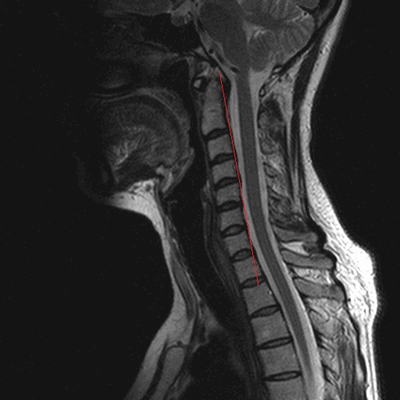

МРТ шейного отдела позвоночника: оценка лордоза, сагиттальная плоскость, Т2 последовательность

- искривления позвоночника - кифоз, лордоз, сколиоз;

- дегенеративно-дистрофические заболевания - остеохондроз, остеоартроз, спондилез и пр.;

- компрессию нервного корешка или спинного мозга, стеноз позвоночного канала и пр.